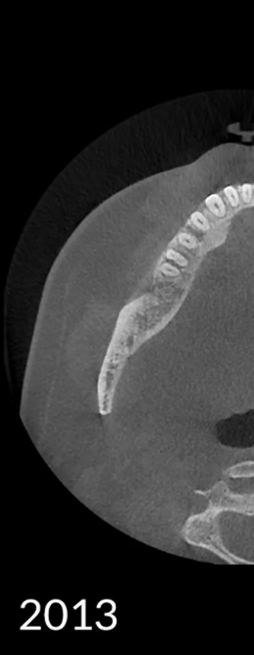

Los algoritmos matemáticos que reflejan las propiedades físicas y el avanzado motor de IA aprendido a partir de varios datos trabajan juntos para reducir el ruido y hacer que las estructuras dentales sean más claras.

Borra los artefactos metálicos y restaura con precisión las estructuras dentales, las coronas metálicas y los implantes basados en principios matemáticos.